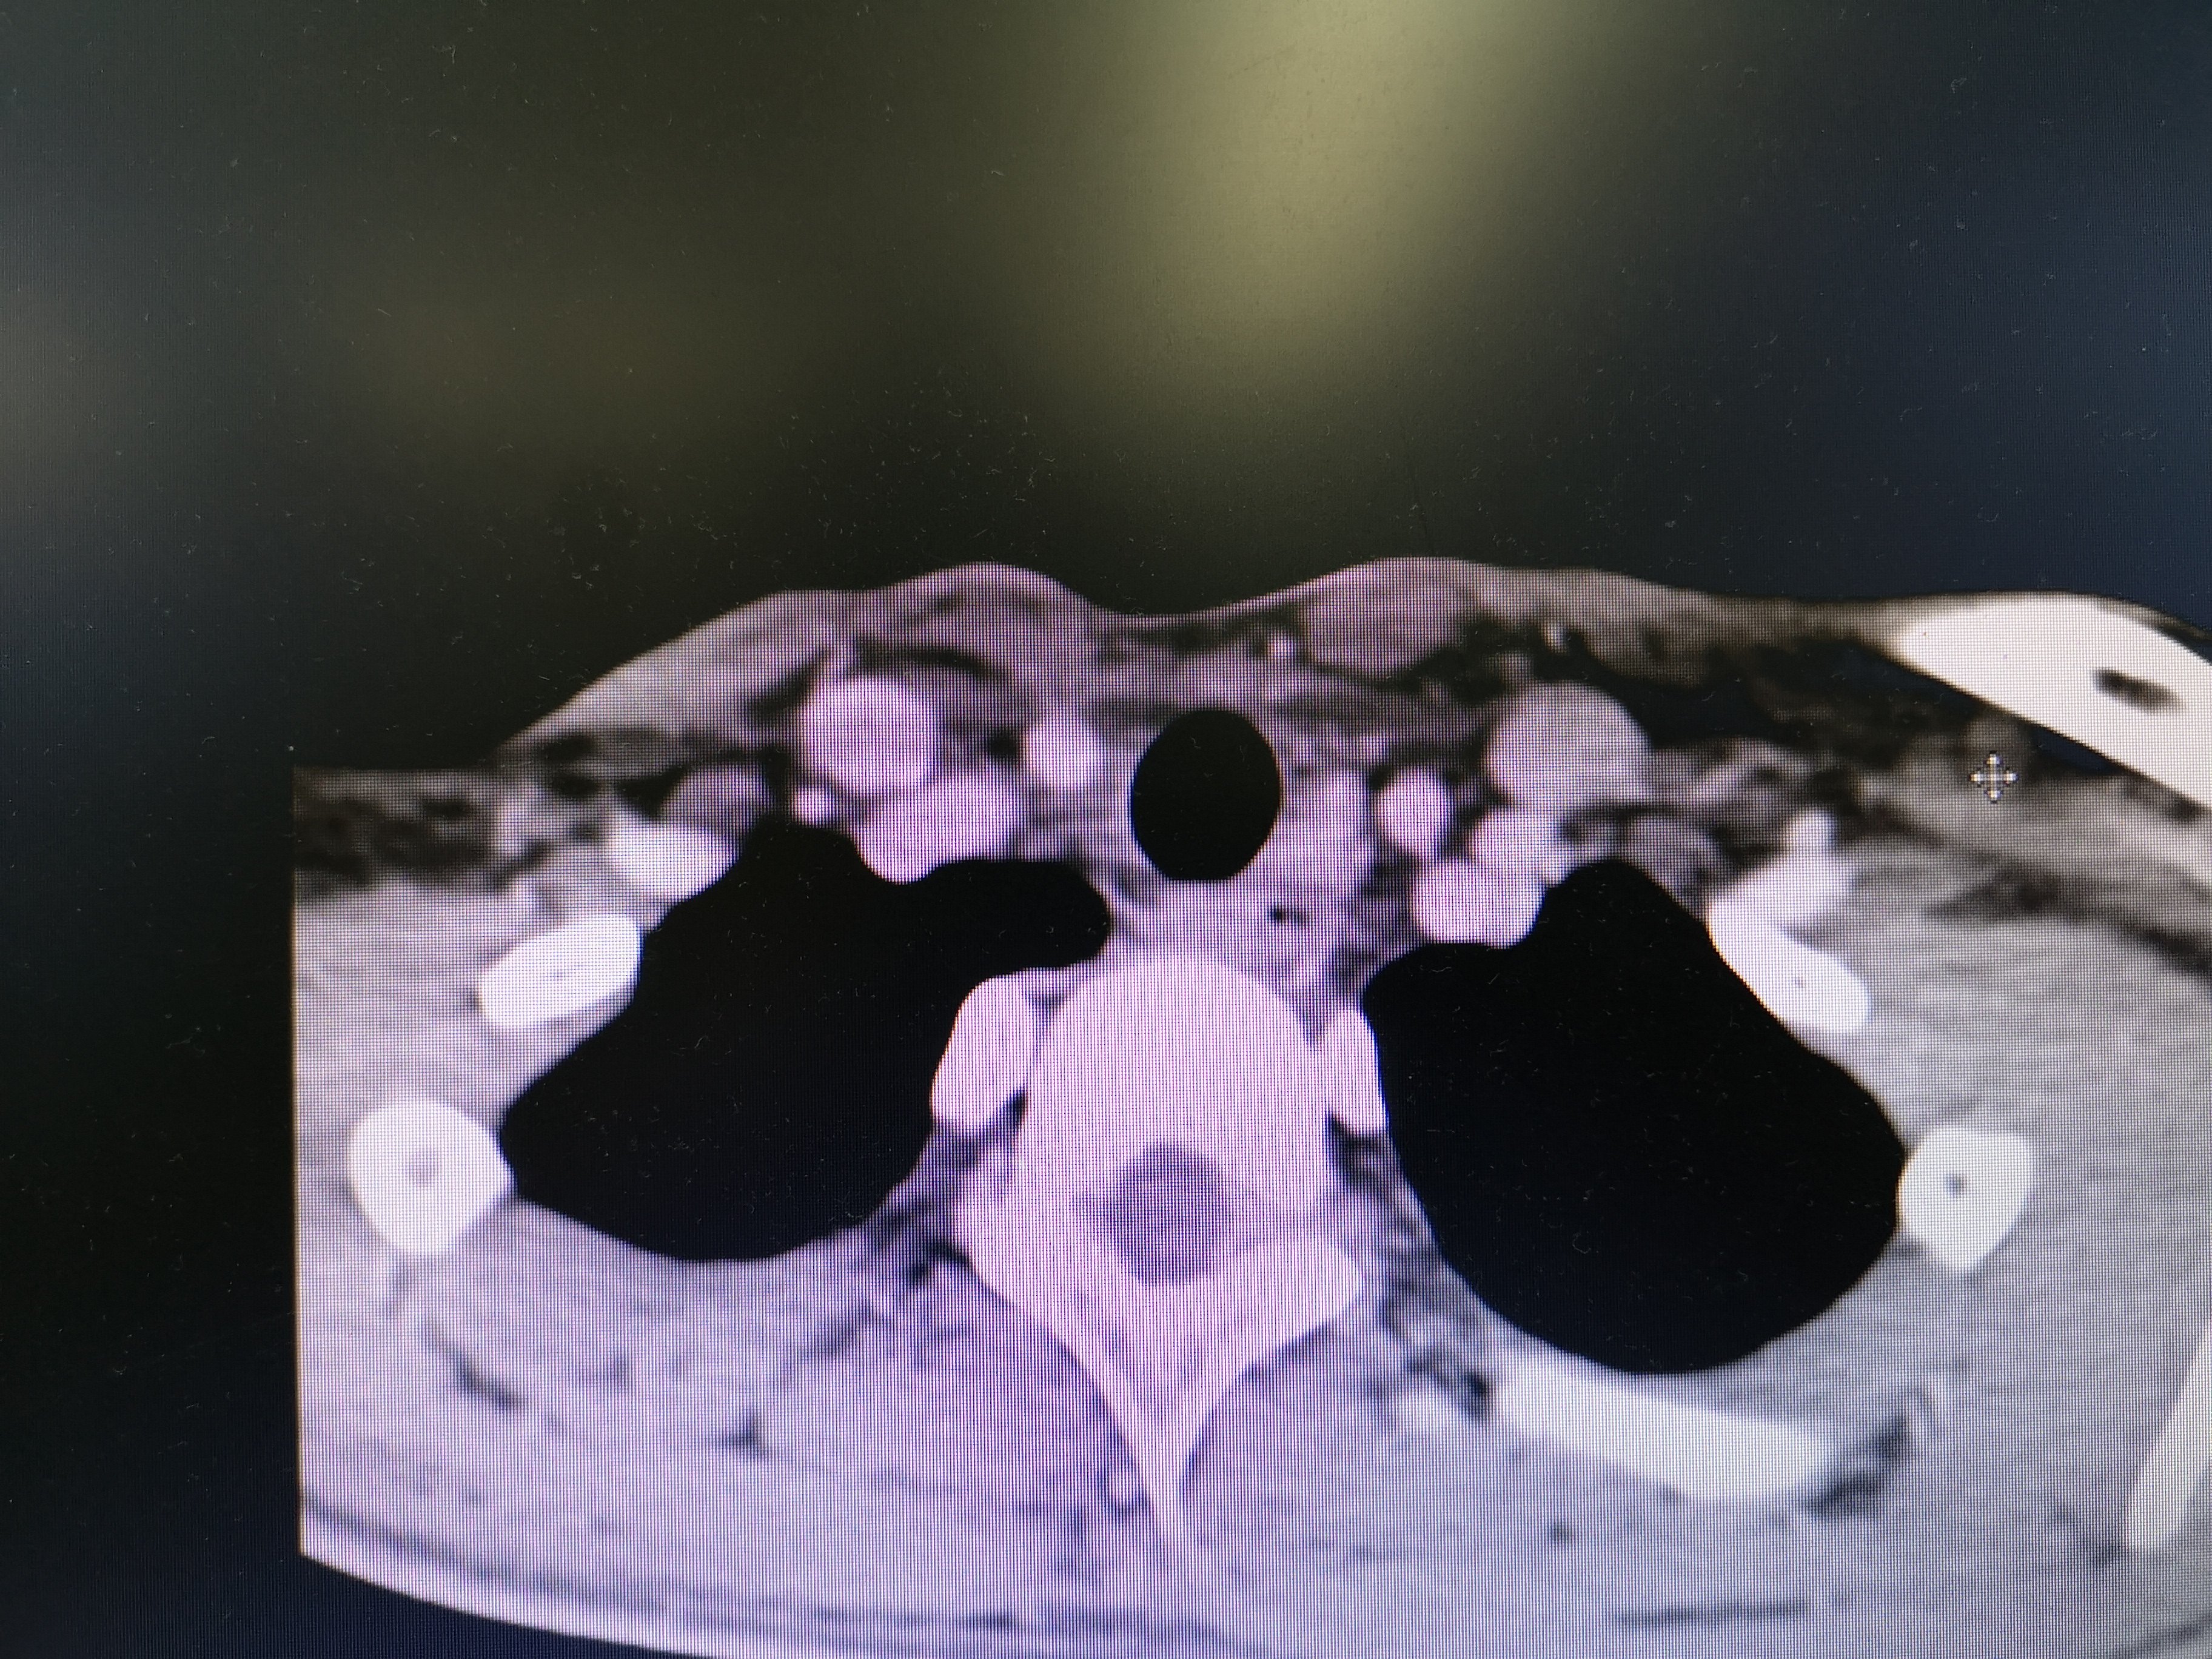

病例2 右2,右4R区,左6区残留,颈部切口清扫,未开胸